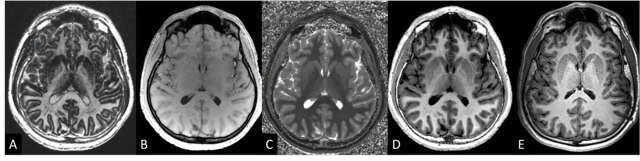

Technique et intérêt des séquences MP2RAGE et MP2RAGE-FLAWS en neuroradiologie clinique

Développées pour obtenir une imagerie T1 homogène et très haute résolution, les séquences MP2RAGE et MP2RAGE-FLAWS s’imposent progressivement comme des outils de référence en neuroradiologie.